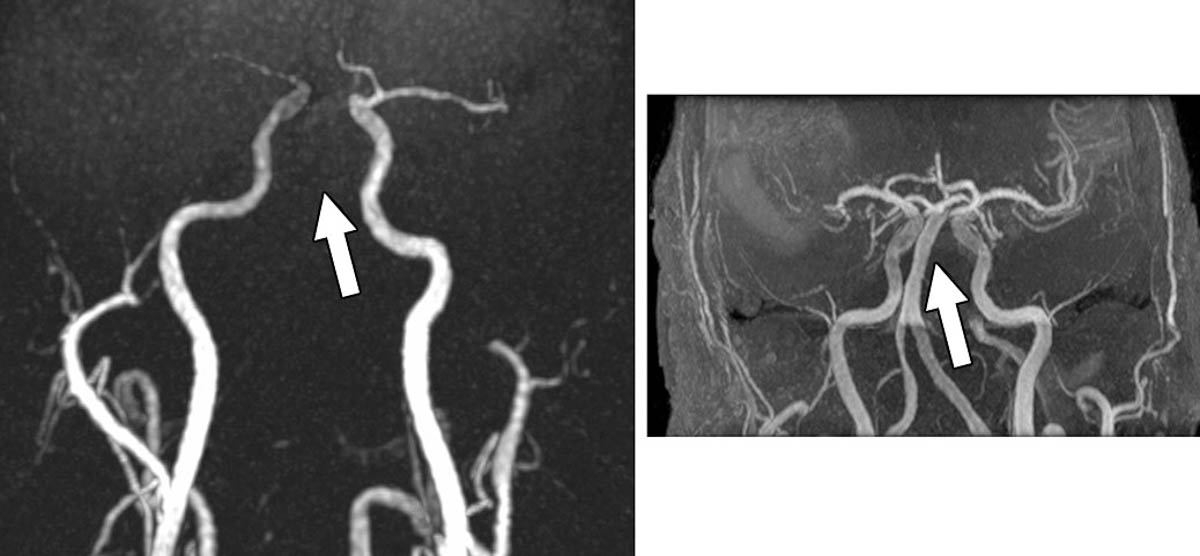

Les séquences conventionnelles préférées en angio-IRM

Pour les séquences d’angio-IRM, les séquences conventionnelles obtiennent une note plus élevée pour toutes les mesures de qualité d’image. Les neuroradiologues préfèrent les séquences conventionnelles dans 69 % des cas, contre 4 % pour les séquences Silent. Dans certains cas, les artefacts sur les images Silent entraînent une diminution du calibre des vaisseaux, des irrégularités et même l’absence de vaisseaux, rapportent les auteurs.